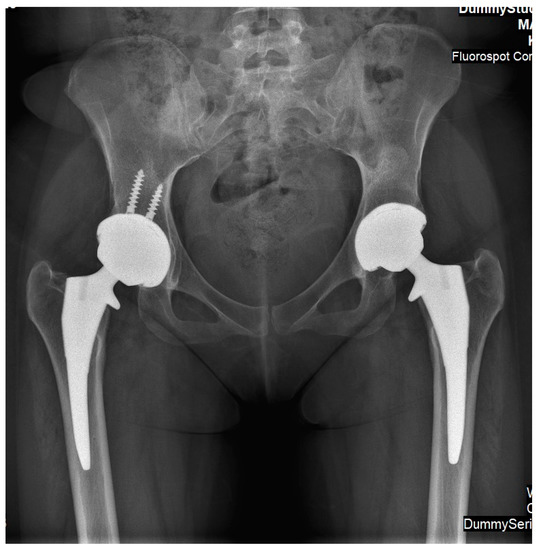

Figure 5.

An antero-posterior X-ray of pelvis and hip joints of Case 2. It was performed after she underwent simultaneous bilateral hip arthroplasty. Implants are similar; however, acetabular cup on right side was augmented using two screws (based on surgeons’ preferences).